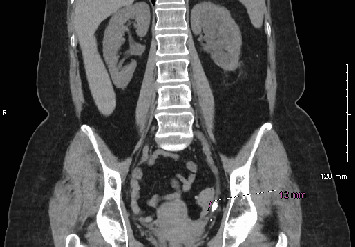

尿脓毒症是一种源自泌尿道的严重感染,可能危及生命。我们报告了一位56岁的女性患者,她在15天内两次出现尿脓毒症,每次发作都发生在支架移除后不久。输尿管镜下支架置入治疗左侧远端输尿管12毫米结石。尽管在影像学检查未发现结石残留后才取出支架,但不久后脓毒症发生,导致再次输尿管镜检查和支架置入。在第二次支架移除之前,影像学再次证实没有结石存在,但在第二次支架移除后,她再次出现败血症。两例败血症住院期间的进一步影像学检查显示结石碎片和肾积水,这在办公室评估中被遗漏。这个病例强调需要更有效的成像技术来检测残留的结石。输尿管镜下输尿管结石治疗后放置支架的决定也应仔细考虑,即使是低风险患者,以减少感染风险。

Urosepsis, a severe infection originating from the urinary tract, can be life-threatening. We present the case of a 56-year-old female who developed urosepsis twice within 15 days, each episode occurring shortly after stent removal. Ureteroscopy with stent placement was initially performed to treat a 12-mm stone in the distal left ureter. Although the stent was removed only after imaging showed no residual stones, sepsis developed shortly after, leading to another ureteroscopy and stent placement. Before the removal of the second stent, imaging again confirmed no stones were present, yet she experienced sepsis once more following the second stent removal. Further imaging studies during hospital admission for both episodes of sepsis revealed stone fragments and hydronephrosis which were missed during office evaluations. This case highlights the need for more effective imaging techniques to detect residual stones. The decision to place a stent after ureteroscopy for ureteral stone treatment should also be carefully considered, even for low-risk patients, to reduce infection risk.